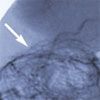

Repeated abdominal CT showed thrombosis of the superior mesenteric vein and fluid around the spleen (Figure 1). The thrombus extended into the portal vein. An abdominal angiogram demonstrated thrombosis of the superior mesenteric vein as well as diffuse venous collaterals, consistent with subacute mesenteric venous thrombosis (Figure 2).